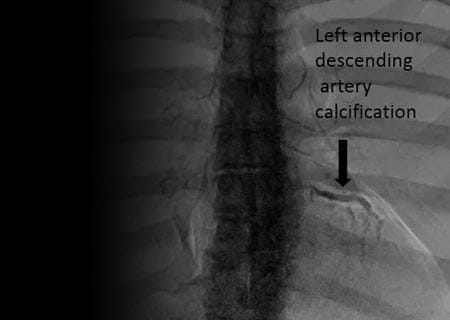

Tomosynthesis: Is It Reaching a Tipping Point?

3-D mammography superior to traditional imaging for both dense-breasted and nondense-breasted women, JAMA study finds